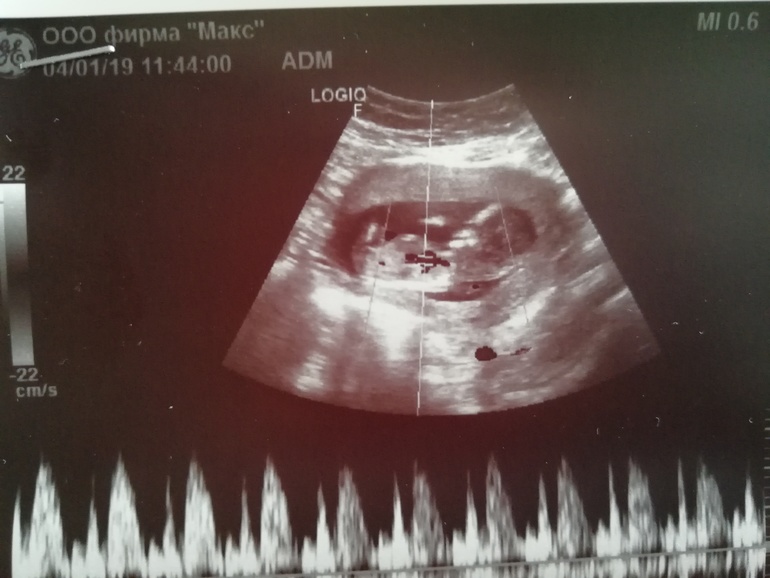

Пол малышаДевчули, кто понимает, скажите, ну похоже же на девочку? Я все ищу в интернете похожие снимки😄 врач сказала что мальчик, но я не верю, в 20 недель точнее будет видно, если я дотерплю😄

Вот эта беленькая черточка в районе ног, это же и есть половой бугорок?

Судя по этой картинке, то у меня девочка, так как на картинке бугорок прям стоит, а на моей фотографии параллелен позвоночнику. Но я что-то всего начиталась в интернете и думаю что нужно просто пойти через 3-4 недели на УЗИ. Тогда уже точно скажут.

Не хочу расстраивать, но у Вашей "девочки" коки видны... Специально фото увеличила, детально рассмотреть.🙊

Тут сомнительно пока. У меня со старшим сыном прям вверх пипка уверенно торчала, без сомнений было. Со вторым сыном были сомнения у врача, сейчас на 90% девочка, но половой бугорок смотрит вниз. Тут тоже вроде угол девчачий, но я почему-то в сомнениях, бугорок ли это.

Если бугорок, обведенный Вами кружочком и есть половой бугорок, то это девочковый пирожок. Пусть Ваши желания исполнятся.